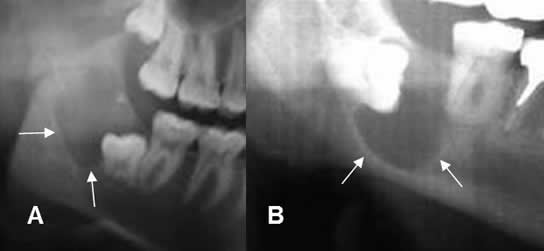

Fig 58. Quiste dentígero.

A y B: Ortopantografía. Lesiones radiolúcidas, de bordes bien definidos y escleróticos, (Líneas delgadas), en relación a la corona de los dientes incluidos, por quistes dentígeros.

Fig 59. Quiste dentígero.

Ortopantografía. Lesión quística, de bordes escleróticos y bien definidos en la rama mandibular. (Flechas delgadas). En su interior se identifica una pieza dental. (Flecha gruesa).